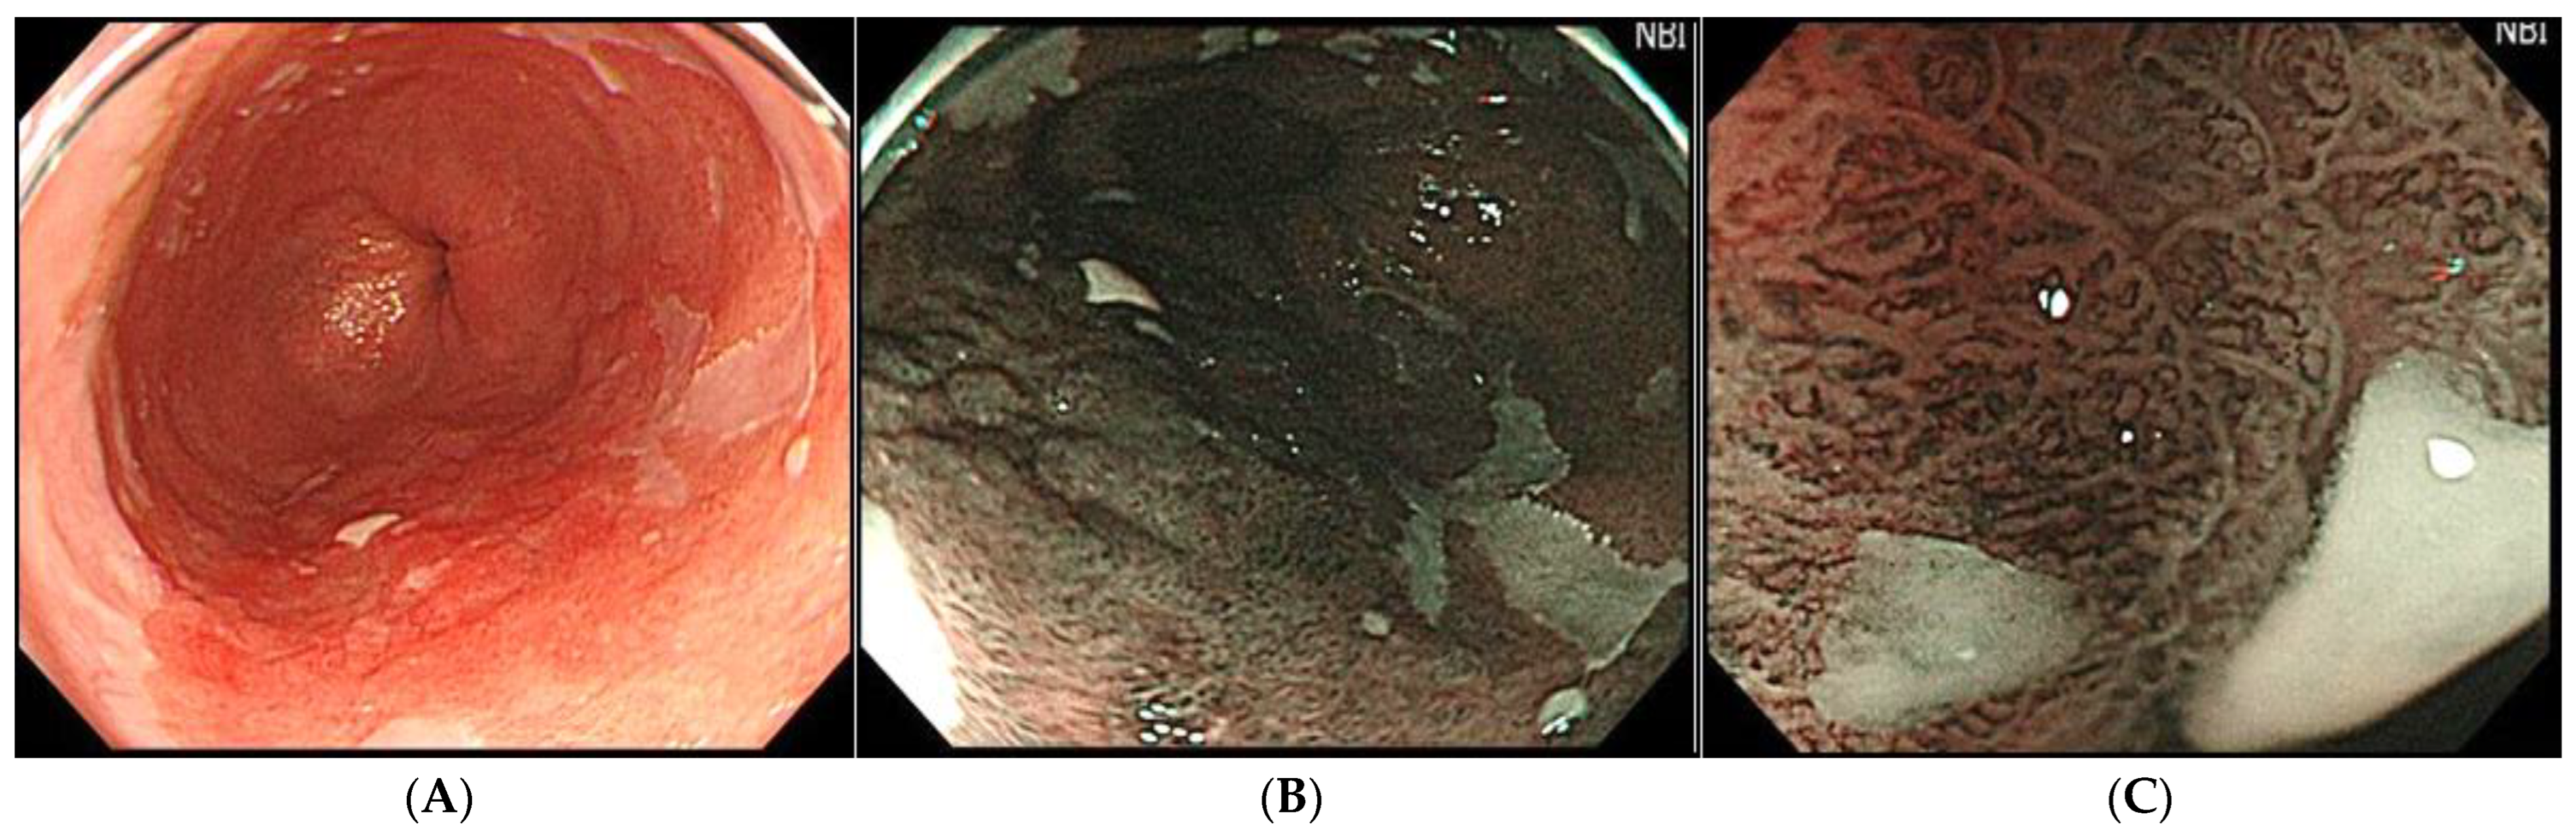

- Hamamoto, Y.; Endo, T.; Nosho, K.; Arimura, Y.; Sato, M.; Imai, K. Usefulness of narrow-band imaging endoscopy for diagnosis of Barrett?s esophagus. J. Gastroenterol. 2004, 39, 14–20. [Google Scholar] [CrossRef]

- Konda, V.J.A.; Hart, J.; Lin, S.; Tretiakova, M.; Gordon, I.O.; Campbell, L.; Kulkarni, A.; Bissonnette, M.; Seewald, S.; Waxman, I. Evaluation of microvascular density in Barrett’s associated neoplasia. Mod. Pathol. 2013, 26, 125–130. [Google Scholar] [CrossRef][Green Version]

- Goda, K.; Takeuchi, M.; Ishihara, R.; Fujisaki, J.; Takahashi, A.; Takaki, Y.; Hirasawa, D.; Momma, K.; Amano, Y.; Yagi, K.; et al. Diagnostic utility of a novel magnifying endoscopic classification system for superficial Barrett’s esophagus-related neoplasms: A nationwide multicenter study. Esophagus 2021, 18, 713–723. [Google Scholar] [CrossRef]

- Struyvenberg, M.R.; De Groof, A.J.; van der Putten, J.; van der Sommen, F.; Baldaque-Silva, F.; Omae, M.; Pouw, R.; Bisschops, R.; Vieth, M.; Schoon, E.J.; et al. A computer-assisted algorithm for narrow-band imaging-based tissue characterization in Barrett’s esophagus. Gastrointest. Endosc. 2021, 93, 89–98. [Google Scholar] [CrossRef]